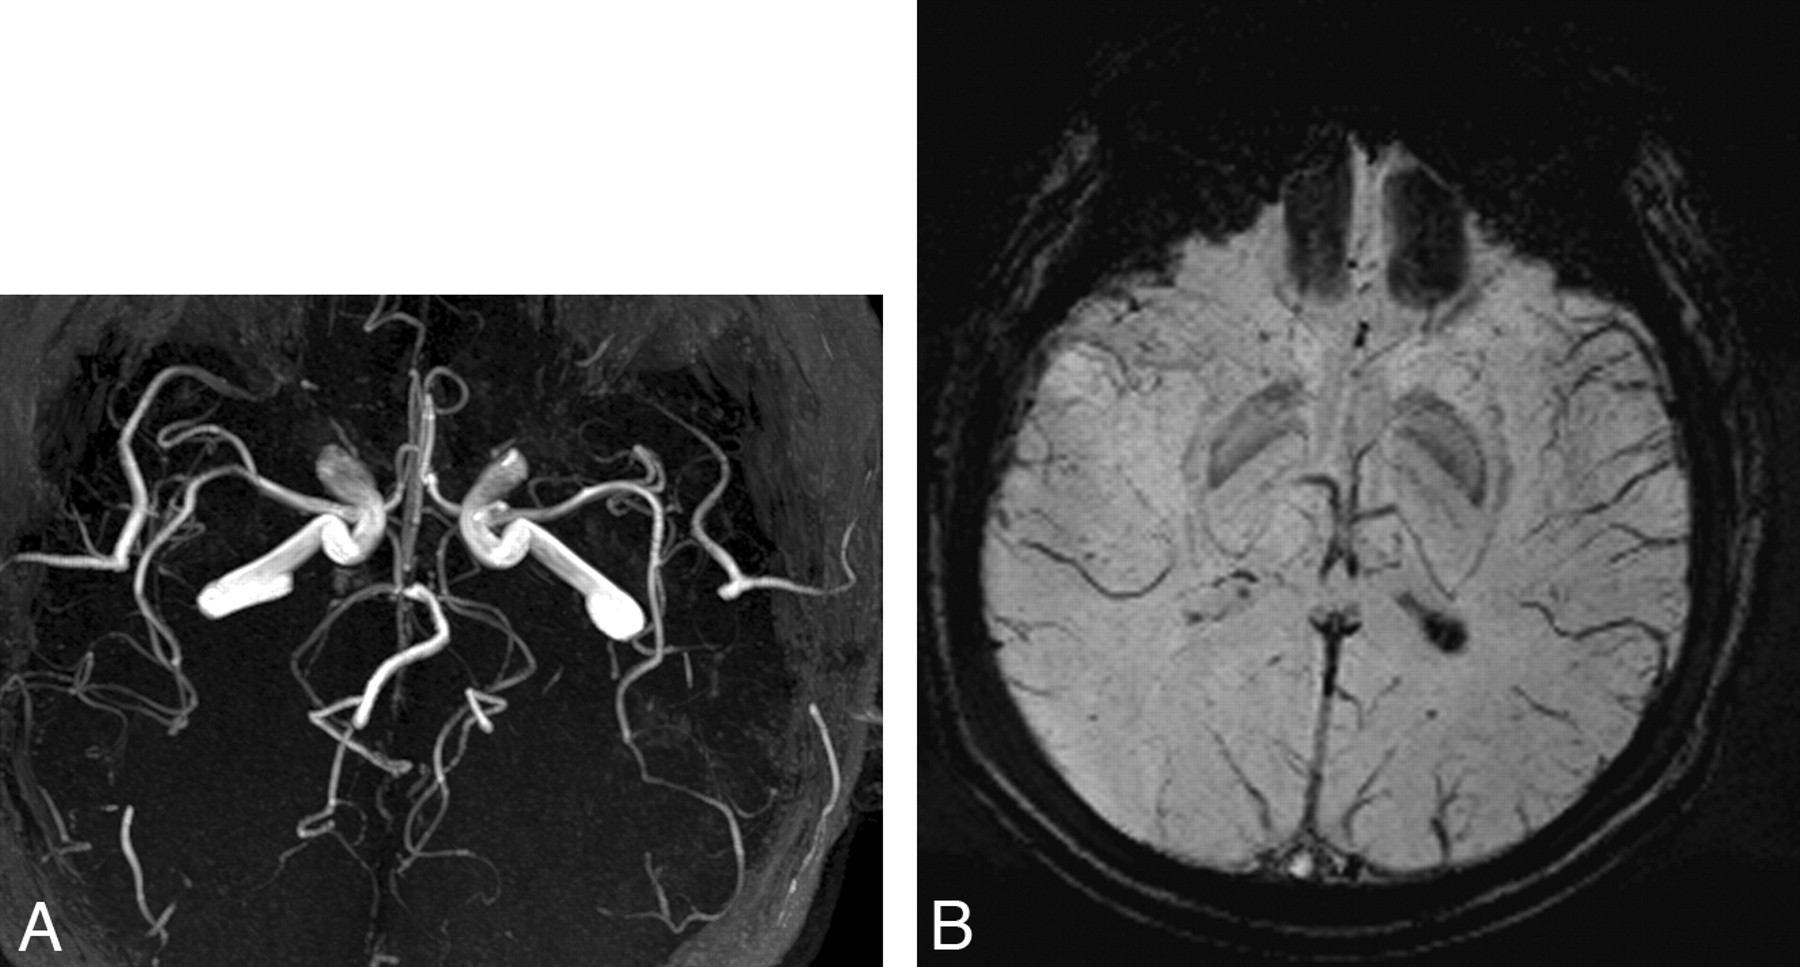

The patient's headache and neurologic deficit resolved completely after 10 hours. Two days after his attack, perfusion MR imaging, MRA (Fig 2A), and SWI (Fig 2B) were repeated; the findings were normal. He was discharged with the diagnosis of migraine with aura without any prophylactic treatment.

A, Normal findings on MRA 2 days after attack. B, Normal SWI finding 2 days after attack.